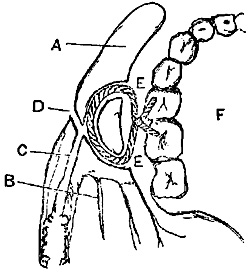

The operation from below (Plate I. fig. 4), Sir Astley Cooper's, is thus described by Mr. Hodgson:[4]—"A semilunar incision is made through the integuments in the direction of the fibres of the aponeurosis of the external oblique muscle. One extremity of the incision will be situated near the spine of the ilium; the other will terminate a little above the inner margin of the abdominal ring. The aponeurosis of the external oblique muscles will be exposed, and is to be divided throughout the extent, and in the direction of the external wound. The flap which is thus formed being raised, the spermatic cord will be seen passing under the margin of the internal oblique and transverse muscles. The opening in the fascia which lines the transverse muscle through which the spermatic cord passes, is situated in the mid space between the anterior superior spine of the ilium and the symphysis pubis. The epigastric artery runs precisely along the inner margin of this opening, beneath which{11} the external iliac artery is situated. If the finger therefore be passed under the spermatic cord through this opening in the fascia, it will come in immediate contact with the artery which lies on the outside of the external iliac vein. The artery and vein are connected by dense cellular tissue, which must be separated to allow of the ligature being passed round the former."

Operation of Ligature of the Femoral—Scarpa's Space.—The patient being placed on his back, and being brought very thoroughly under chloroform, the knee of the affected limb should be bent at an angle of about 120°, and supported on a pillow. Having previously ascertained the angle of junction of the sartorius and adductor, the surgeon should make an incision (Plate I. fig. 5) just over the pulsations of the vessel, in the middle line of the space, having its lower end quite over the sartorius muscle, and its upper one, at a distance from two and a half to three and a half inches, varying according to the amount of fat and muscle. The saphena vein can generally be recognised, and is almost always safe out of the way of this incision at its inner side.

The first incision should divide the skin, superficial fascia, and fat, quite down to the fascia lata. The edges of the wound being held apart, the fascia should be carefully divided, and the sartorius exposed; its fibres can generally be easily enough recognised by their oblique direction; once recognised, the fascia should be dissected from it till its inner edge be gained, the corner of which should then be turned so that it may be held outwards by an assistant with a blunt hook. The sheath of the vessels is now exposed, and after having thoroughly{19} satisfied himself of the position of the artery by the pulsation, the surgeon should carefully raise a portion of the sheath with the dissecting forceps, and open it freely enough to allow the coats of the artery to be distinctly seen. If the parts are deep, as in a fat or muscular patient, great advantage will be gained by seizing one edge of the sheath by a pair of spring forceps, and committing it to the care of an assistant, while the operator holds the other in his dissecting forceps; there is thus no fear of losing the orifice of the sheath, which without this precaution may easily happen, from the parts being confused with blood, or the position altered by movements of the patient. Now comes the stage of the operation on which, more than on anything else, success or failure depends. A small portion of the vessel must be cleaned for the reception of the ligature, and it must be thoroughly cleaned, so that the needle may be passed round it without bruising of the coats, or rupture of an unnecessary number of the vasa vasorum by rough attempts to force a passage for it. Hence all compromises, such as blunted instruments, silver knives, and the like, are dangerous, for in trying to avoid the Scylla of wounding the artery, they fall into the Charybdis, on the one hand, of isolating too much of the vessel and causing gangrene from want of vascular supply, or, on the other, expose the vein to the danger of injury by the aneurism-needle in their attempts to force it round an uncleaned vessel.

The needle should in most cases be passed from the inner side, care being taken to avoid including the vein which is on the inner side and behind the vessel; the internal saphenous nerve, if seen, should be avoided. The needle must not be passed quite round the vessel raising it up, still less must the vessel be held up on the needle, as used to be done, as if the surgeon was surprised at his own success, but the needle should be passed just far enough to expose the end of the ligature,{20} which must be seized by forceps and cautiously drawn through. It must then be tied very firmly and secured with a reef knot.

The limb being laid as before on the outside, and slightly bent, the skin shaved and the pulsation of the artery detected, an incision (Plate I. fig. 6) must be made from the lower edge of the sartorius muscle just as it crosses the vessel, along the course of the vessel, avoiding if possible the internal saphena vein.

The sartorius when exposed must be drawn inwards. The fibrous canal filling the interspace between the abductor magnus and vastus internus is then recognised, and must be fairly opened; the artery is now seen lying{22} in it, and over the vein which is posterior to it, but projects slightly on its outer side; the internal saphenous nerve is lying on the artery. The needle is best passed from without inwards so as to avoid the vein. The anastomotica magna is sometimes a large trunk, and has been mistaken for the femoral in this situation, and tied instead of it.